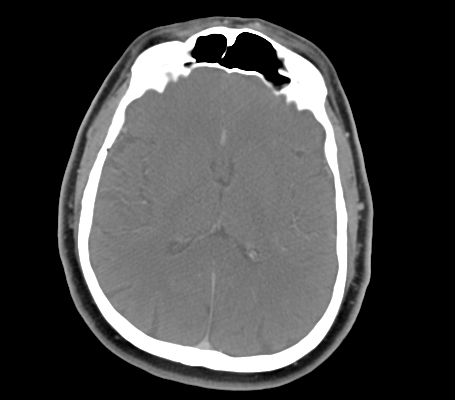

Frontal Sinus

Temporalis Muscle